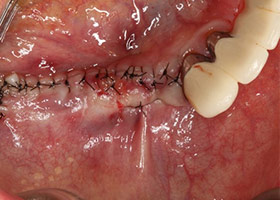

7.進行角質化牙齦移植手術。

8.牙齦手術完成。